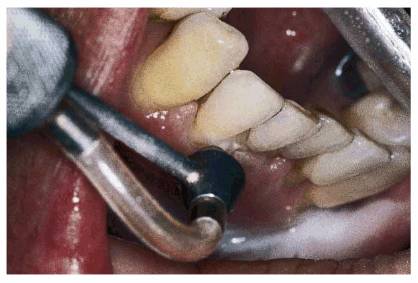

procedure can be seen in Figures 17-8A

and B 17-8C 17-8D 17-8E 17-8F 17-8G 17-8H and I, which show a 45-year-old man with

evidence of gingival and incisal abrasion, erosion, and abfraction. It is

Figure 17-8A and B: This 45-year-old man shows extreme tooth loss due to combination lesions both gingivally and incisally of abrasion, erosion, and abfraction.

Figure 17-8C: An air polisher is used to remove stain.

Figure 17-8D: Note how clean the teeth appear after a thorough prophylaxis with an air polisher.